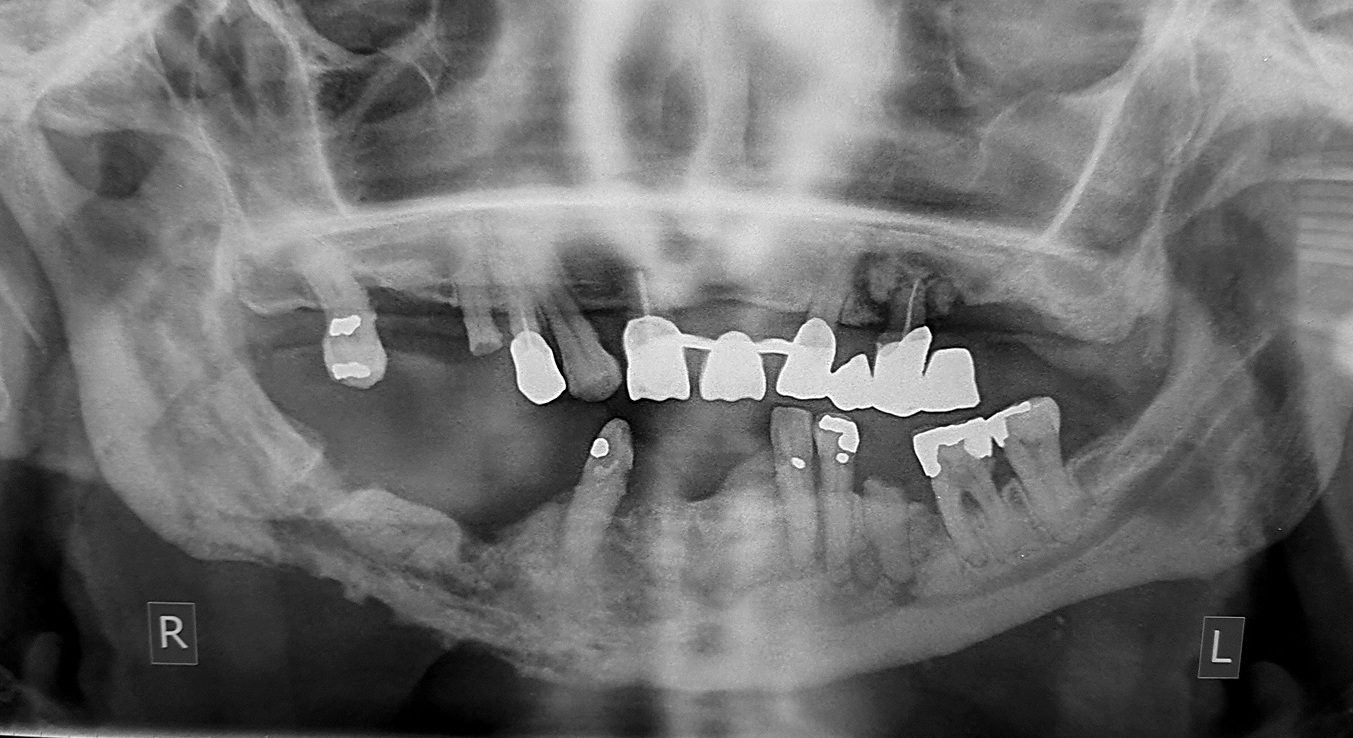

•  Ακτινογραφικά ευρήματα: Συνήθως παρατηρείται οστεολυτική βλάβη με ασαφή και σκοροφαγωμένα όρια, η οποία έχει προκαλέσει λύση και διάτρηση των συμπαγών πετάλων της γνάθου. Συχνά διακρίνεται εντοπισμένη ή εκτεταμένη σκλήρυνση του οστού, καθώς και περιοστική εναπόθεση. Επιπλέον, εντός των οστεολυτικών βλαβών μπορεί να παρατηρηθούν διάσπαρτα οστικά απολύματα, τα οποία δημιουργούν την εικόνα της μικτής αλλοίωσης. Σε προχωρημένα στάδια, οι βλάβες μπορούν να διηθήσουν τα παρακείμενα ανατομικά μόρια.

Οστεονέκρωση της άνω και της κάτω γνάθου λόγω λήψης διφωσφονικών